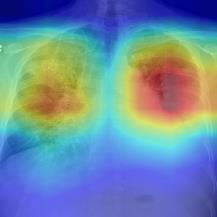

Thoracic disease detection from chest radiographs using deep learning methods has been an active area of research in the last decade. Most previous methods attempt to focus on the diseased organs of the image by identifying spatial regions responsible for significant contributions to the model's prediction. In contrast, expert radiologists first locate the prominent anatomical structures before determining if those regions are anomalous. Therefore, integrating anatomical knowledge within deep learning models could bring substantial improvement in automatic disease classification. This work proposes an anatomy-aware attention-based architecture named Anatomy X-Net, that prioritizes the spatial features guided by the pre-identified anatomy regions. We leverage a semi-supervised learning method using the JSRT dataset containing organ-level annotation to obtain the anatomical segmentation masks (for lungs and heart) for the NIH and CheXpert datasets. The proposed Anatomy X-Net uses the pre-trained DenseNet-121 as the backbone network with two corresponding structured modules, the Anatomy Aware Attention (AAA) and Probabilistic Weighted Average Pooling (PWAP), in a cohesive framework for anatomical attention learning. Our proposed method sets new state-of-the-art performance on the official NIH test set with an AUC score of 0.8439, proving the efficacy of utilizing the anatomy segmentation knowledge to improve the thoracic disease classification. Furthermore, the Anatomy X-Net yields an averaged AUC of 0.9020 on the Stanford CheXpert dataset, improving on existing methods that demonstrate the generalizability of the proposed framework.